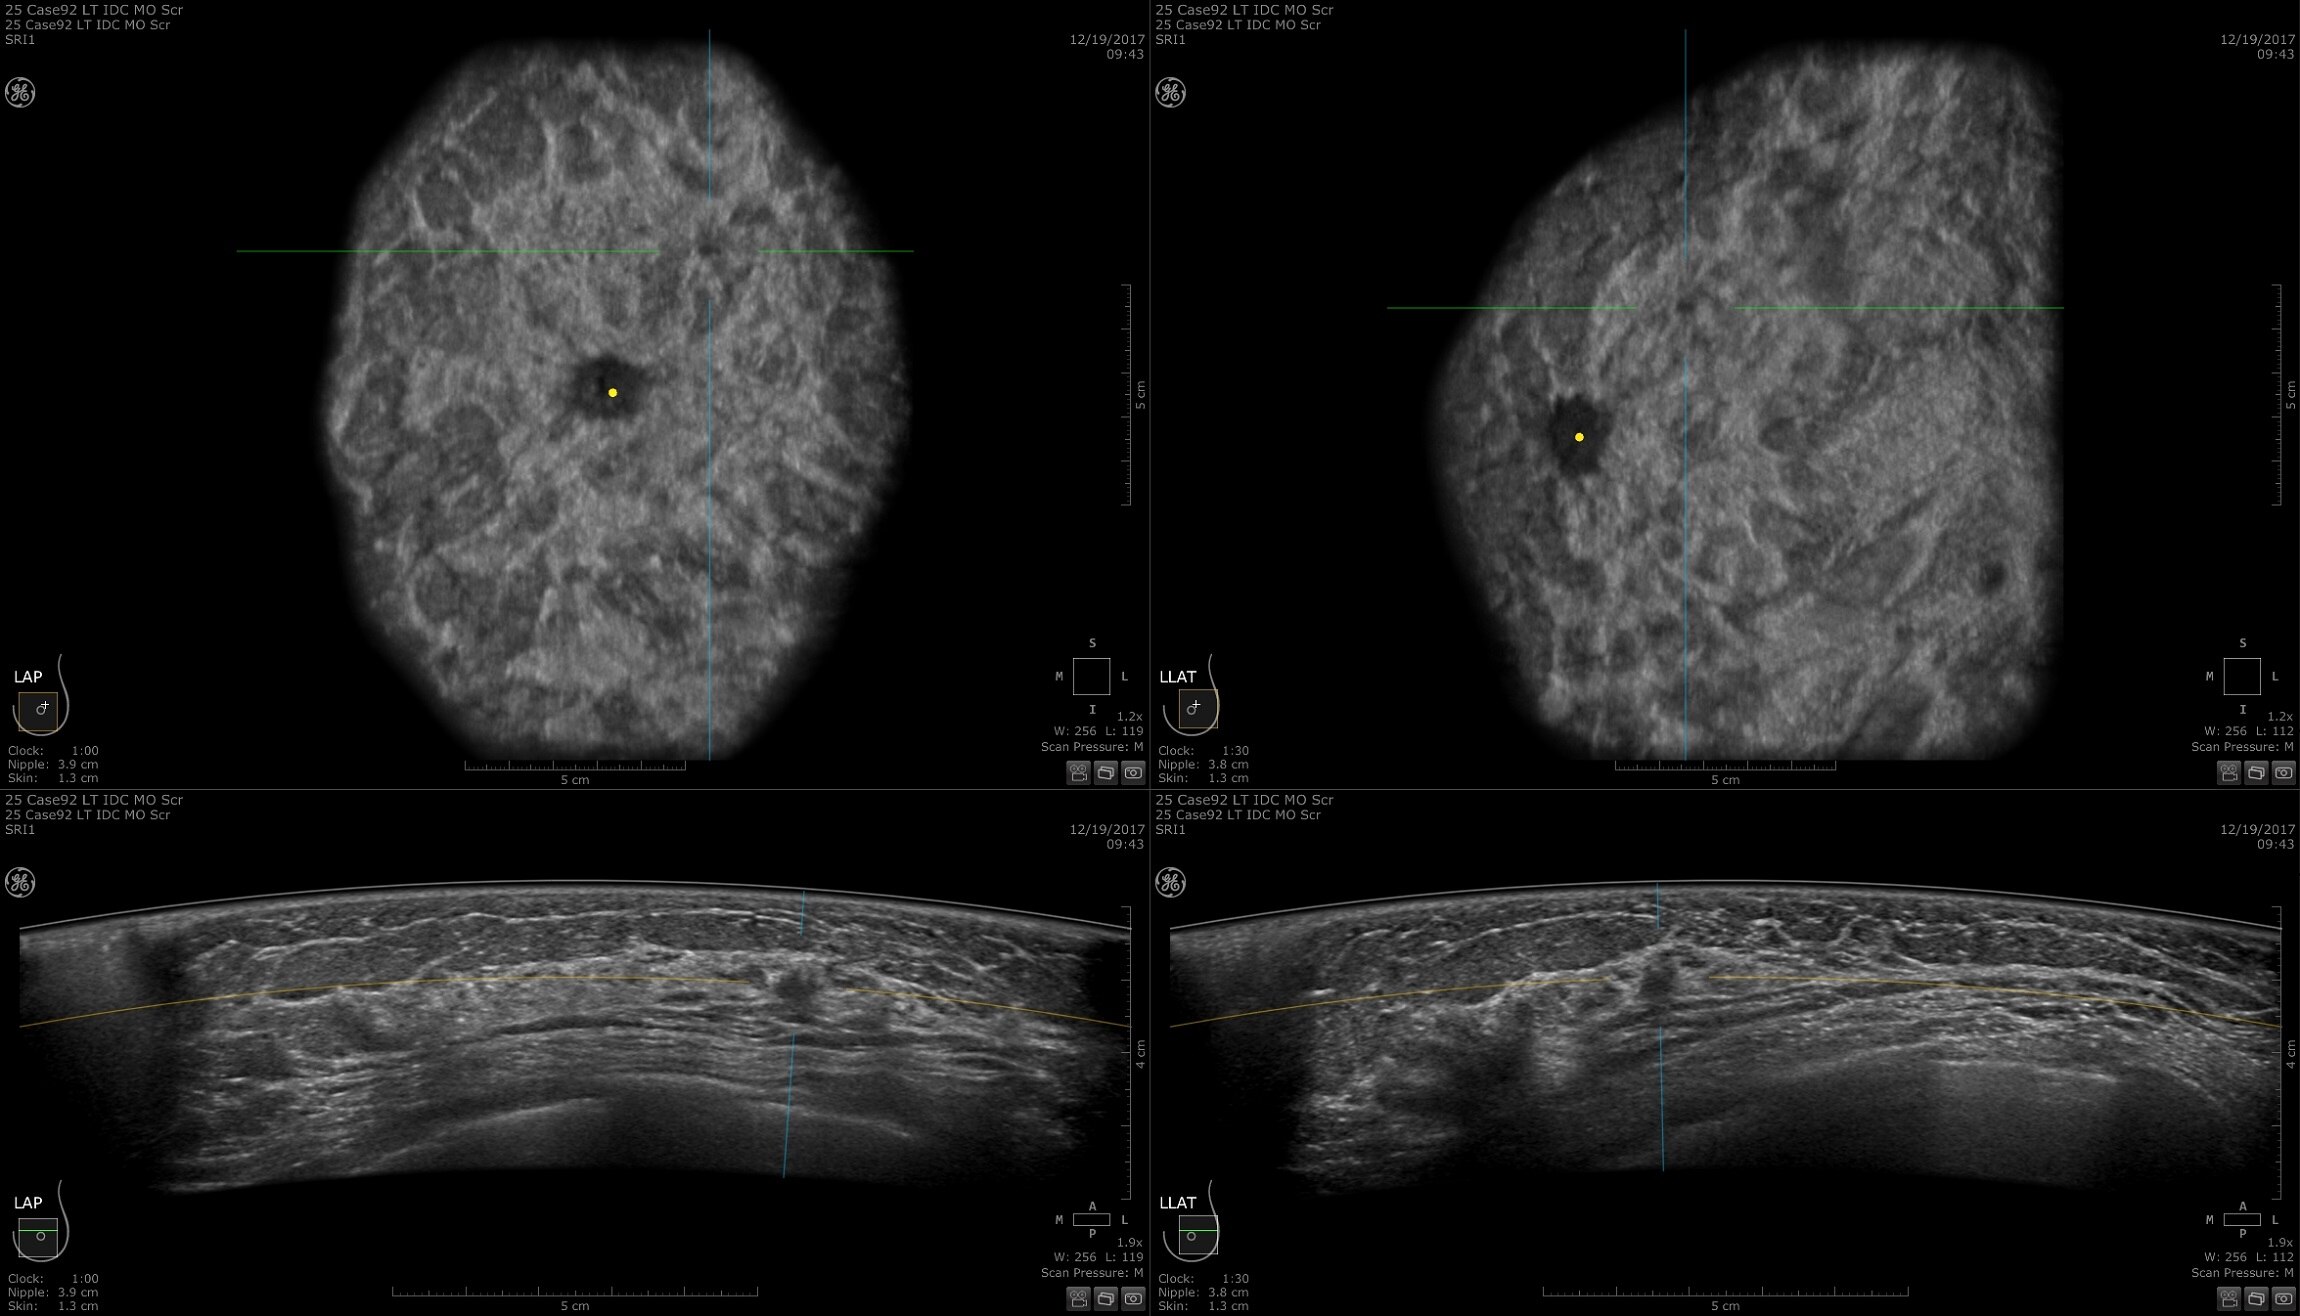

Dense breast tissue and cancer appear white on a mammogram, potentially camouflaging small cancers. Invenia ABUS 2.0, is specifically designed to help clinicians find cancers that may be hidden on mammography1,2.

SCREENING

The power of early cancer detection

Supplemental screening with Invenia ABUS 2.0 transforms breast care from reactive to proactive. When used in addition to mammography, Invenia ABUS 2.0 can improve breast cancer detection by 55 percent over mammography alone5. Women whose breast cancer is detected at an early stage have a 90% or higher survival rate6.